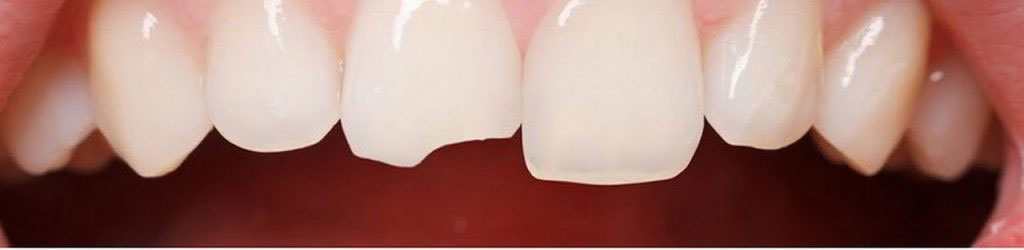

Estetik Kaplamalar

Dişler üzerinde meydana gelen kırık, çatlak, çürük ve çarpma gibi etkiler sonucunda diş üzerine kaplama yapılması ihtiyacı ortaya...

Devamını Oku

Estetik Dolgular

Estetik dolgu, dişlerde kompozit malzeme ile kişinin diş rengine sahip dolgu malzemesi kullanılarak daha doğal ve estetik bir gülüş...

Restoratif Diş...

Diş çürükleri diş üzerinde koyu renklenmelerin oluşması ve bu renklenlemeleri oyukların takip etmesi şeklindeki bir süreçtir. Bu süreci...